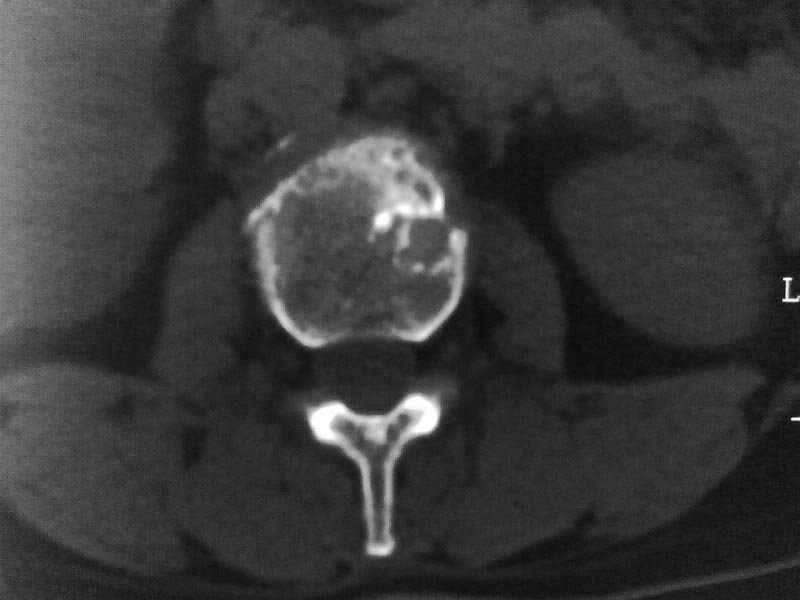

定位相示l2呈楔形改变(ct示陈旧性骨折改变,图像未传),l4.5椎体融合,以下是l4.5ct平扫.请各位看看,

考虑结核(有破坏、硬化及死骨)。

1、三四椎体结核,2、水平骶椎。

2、l3、4椎体结核。

2、l3、4椎体结核。(融合)

就是腰1压缩性骨折,腰3\\4椎体结核(融合),水平骶椎.

腰3、4结核

支持 l1椎体陈旧性压缩性骨折;l3、4椎体结核(融合);水平骶椎。